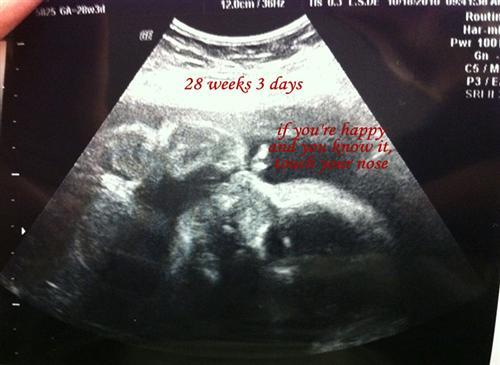

So the great news... she's still a girl! (Whew.) And, she already weighs 2 lbs 11 oz!!!! I can't even believe it! My fluid levels are perfect, and her heartbeat is a strong 151 bpm still. She's measuring 2 days ahead and in the 51st percentile at this point, which the tech said was perfect as well. She's also head down, but my OB says she's still got plenty of time to move around so not to get too excited by that lol.

Apparently, she's lying in there with her feet up by her head lol. I got two cute pictures today that I want to share. One of them, it looks like she has a butterfly on her nose, but it's actually a combo of a hand and a foot.

I annotated the sonos just to make them a tiny bit easier to read...